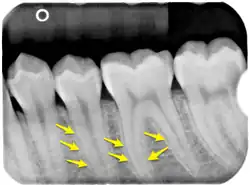

Pfeile markieren exemplarisch eine helle Linie, die Lamina dura.

Als Wurzelhaut (Syn.: Periodontium) wird das Bindegewebe des Zahnhalteapparates bezeichnet. Diese Sharpey-Fasern, zum Periost gehörende Kollagen-Faserbündel, die in der Knochengrundsubstanz befestigt sind, bilden die Verbindung zum Wurzelzement des Zahnes. An ihnen ist der Zahn federnd befestigt und überbrückt den wenige Zehntel Millimeter breiten Spalt (Periodontalspalt) zwischen dem Zahnzement der Zahnwurzel und der knöchernen Wand des Zahnfachs (Alveole), der Lamina dura. Am Zahnhals wird der Periodontalspalt durch den supraalveolären Faserapparat (frühere Bezeichnung: Ligamentum circulare) abgedichtet.